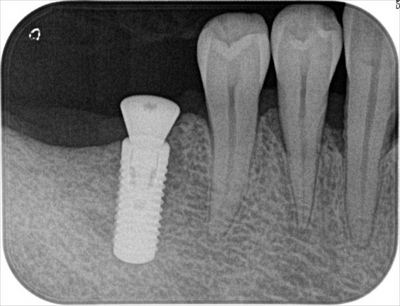

右下には1本埋入しました。Φ4.8mm 長さ12mmです。

O・Hさん、左右3本のインプラントオペお疲れさまでした。